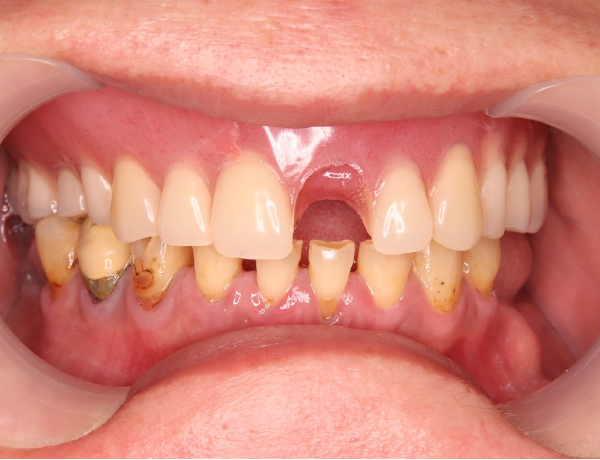

上の入れ歯にヒビが入っている

青い矢印で示している部分に、以前からヒビが入っている状態が確認できます。

このヒビは、前歯が脱落した部分まで一直線に伸びており、入れ歯全体に大きな負担がかかっていたことが分かります。

また、上の入れ歯を詳しく観察すると、歯の並びが左右でアンバランスになっているように見えます。

このような歯の配置のズレがあると、噛み合わせに偏りが生じ、特定の部位に過剰な力が加わることで、入れ歯が割れてしまった可能性が考えられます。

左上の歯が取れてしまっている

左上の前歯が脱落している状態が確認できます。上の噛む面から撮影した写真を見ても分かるように、入れ歯に入っていたヒビのラインが、脱落した前歯の部分まで到達していました

そのため、外から何かが強くぶつかって前歯が取れたのではなく、ヒビが進行して内部で「地割れ」のような状態が生じ、最終的に前歯が自然に脱落したと考えられます。